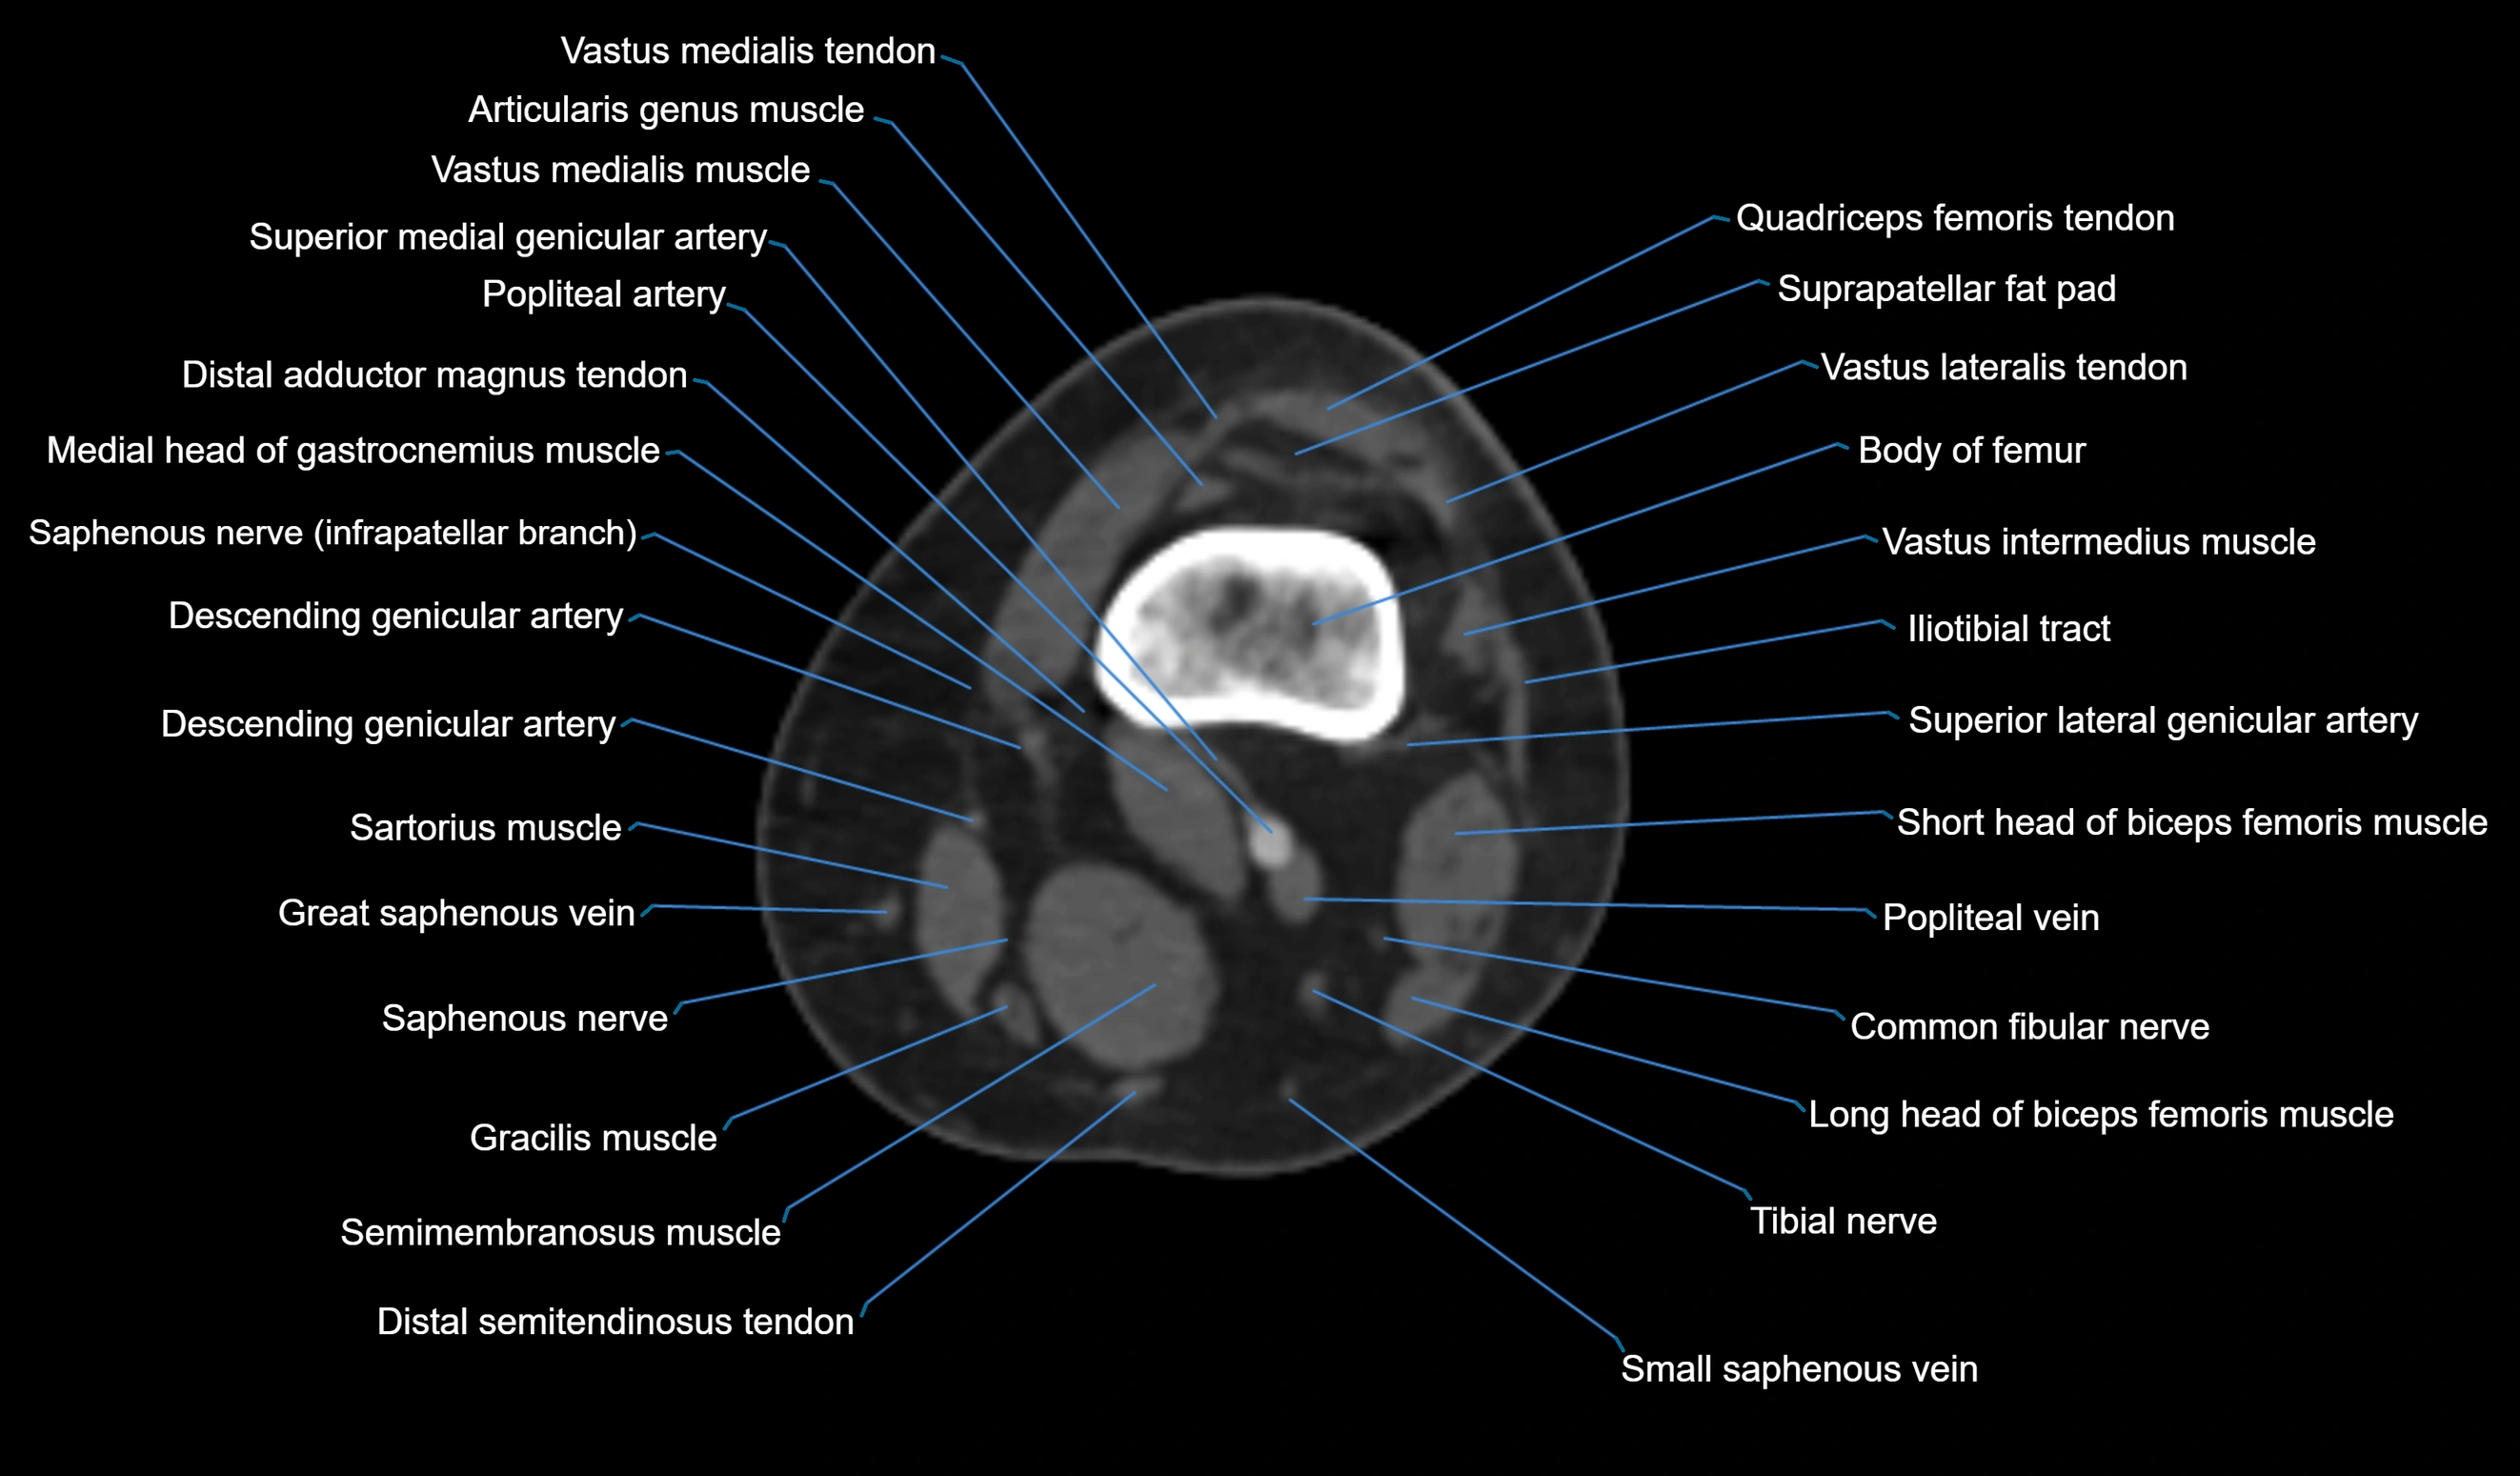

- Biceps femoris muscle (Long head)

- Biceps femoris muscle (Short head)

- Body of femur

- Common fibular nerve

- Distal adductor magnus tendon

- Distal quadriceps femoris tendon

- Distal semitendinosus tendon

- Distal vastus intermedius tendon

- Distal vastus lateralis tendon

- Distal vastus medialis tendon

- Lateral head of gastrocnemius muscle

- Medial head of gastrocnemius muscle

- Popliteal artery

- Popliteal vein

- Saphenous nerve

- Sartorius muscle

- Semimembranosus muscle

- Small saphenous vein

- Superior lateral genicular artery

- Superior medial genicular artery

- Suprapatellar fat pad

- Tibial nerve

- Vastus lateralis muscle

- Vastus medialis muscle